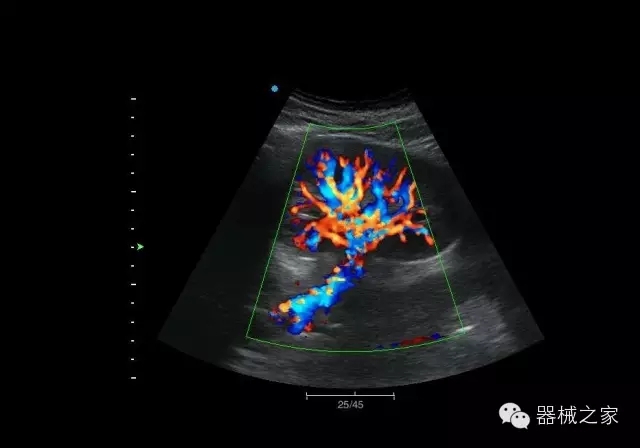

臨床圖片賞析

腎臟血流